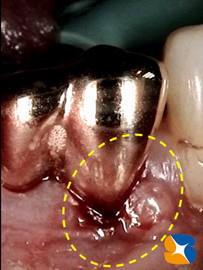

本日も静脈麻酔鎮静法(無料)のもと、抜歯及び大きな膿の袋の摘出を行いました。その結果、予想以上に奥歯を支える骨が欠落していました。

人工の骨(β~TCP)と御自身のアゴ骨の一部をCGFに混在させて、欠落した顎骨を再生させる準備が整いました。